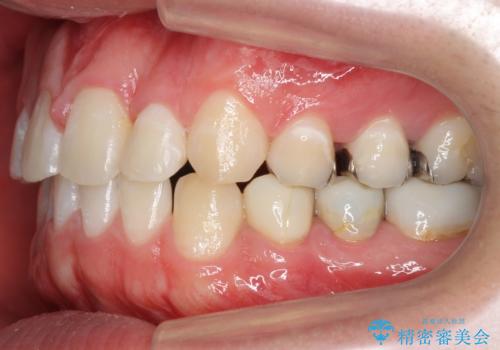

前歯のねじれ 上だけ部分矯正でコストダウン

- 前歯のねじれを部分矯正で治療しました。

奥歯のかみ合わせを変えずに、費用を抑えて短期間に治療したい方におすすめです。

奥歯のかみあわせも問題なく、また、下の前歯のがたつきが元からない場合は上の部分矯正が十分可能です。